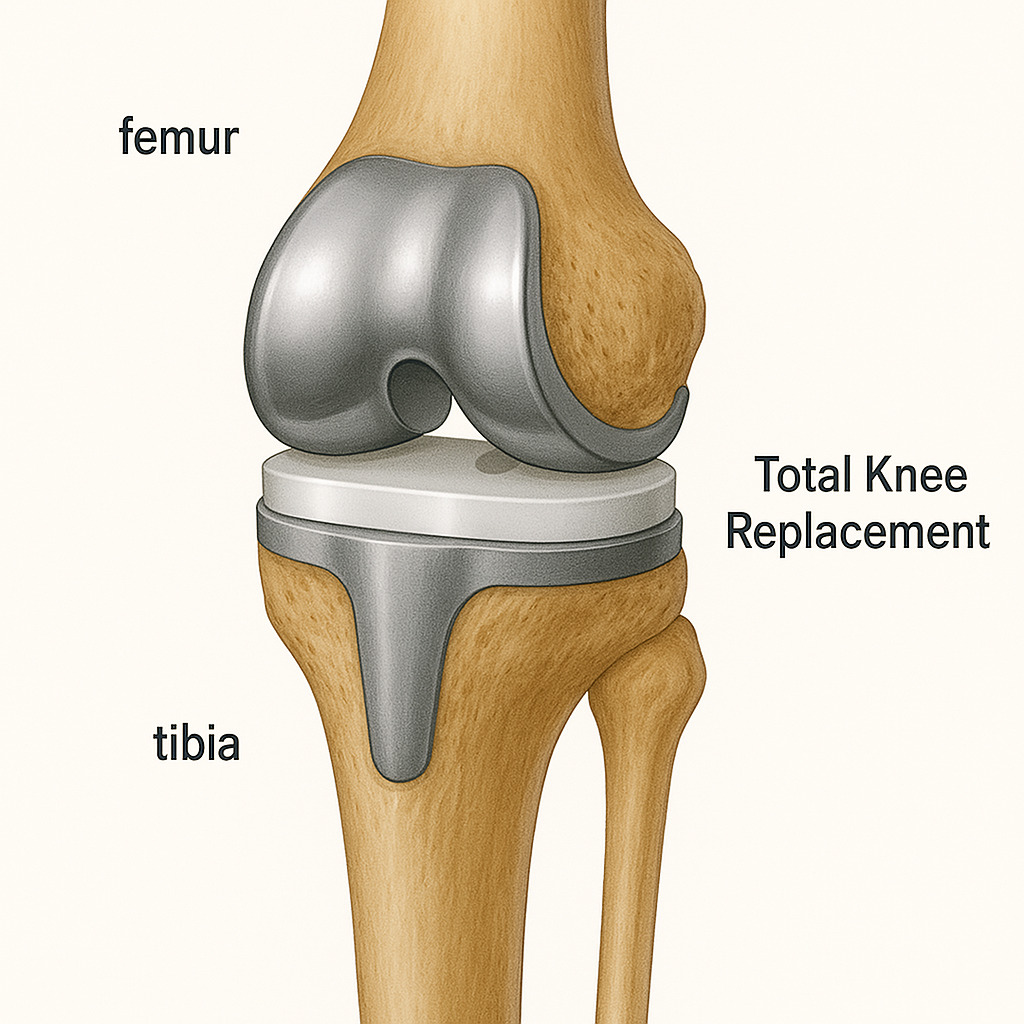

Total Knee Replacement (TKR), also known as knee arthroplasty, is a surgical procedure that replaces the entire knee joint with an artificial prosthesis to relieve pain and improve function. This procedure is typically recommended for individuals suffering from severe knee pain and limited mobility due to conditions such as osteoarthritis, rheumatoid arthritis or traumatic injury.

Resurfacing : Damaged bone and cartilage are removed from the femur, tibia and patella. Metal components are then attached to the ends of these bones and a plastic spacer is placed in between them to create a smooth surface for movement.

A Total Knee Replacement surgery typically involves the following steps :